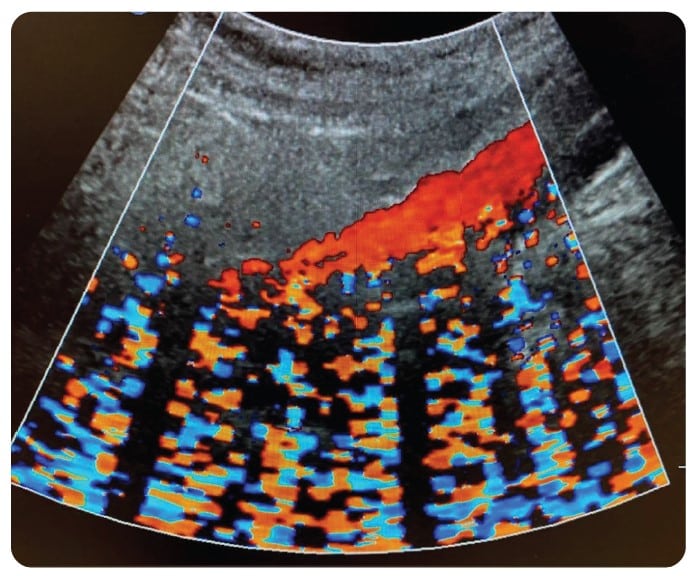

With the proliferation of IoT and wireless technology, the health care setting is even more densely saturated with electronic pollution. Throughout my 30-plus year career in ultrasound, one of the most frequent and most challenging problems to solve has been related to noise artifacts being displayed in an ultrasound image. Typically, these present as axial bands of constant or flashing color in Color Doppler mode. Intense sources of noise can affect 2D imaging in the form of faint gray, semi-axial streaks and/or semi-circular swirls overlaid on the image.